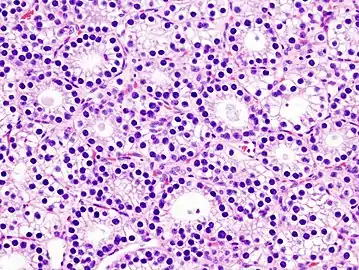

Histopatholgical image of parathyroid adenoma in a patient with primary hyperparathyroidism. Hematoxylin and eosin stain.

Histopatholgical image of parathyroid adenoma in a patient with primary hyperparathyroidism. Hematoxylin and eosin stain. Another view of the same lesion